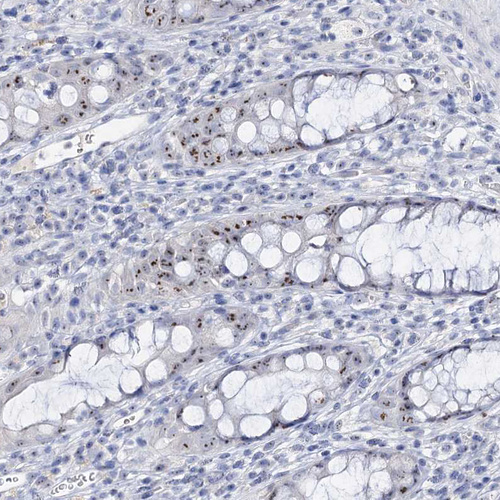

Immunohistochemical staining of human skin shows strong positivity in nucleoli in squamous epithelial cells.